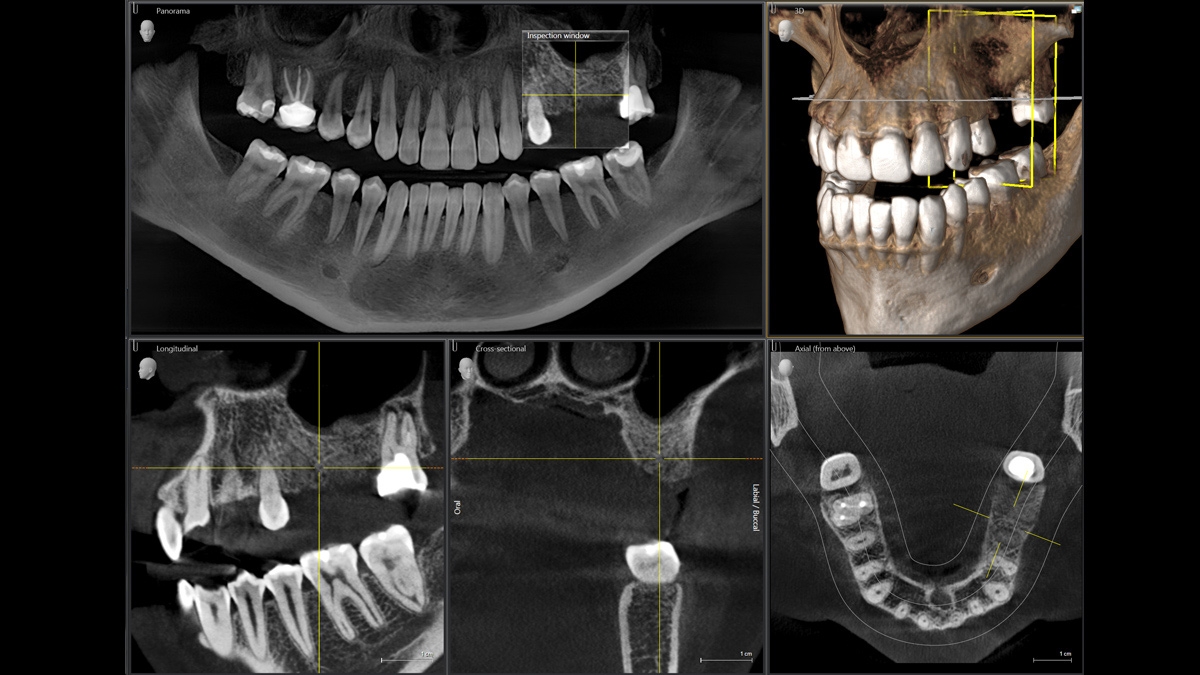

We developed a 10-point concept for easy patient positioning and X-ray imaging. Our concept is primarily about two things: high image quality and comfort for the patient and the assistant. This concept supports and provides the tools needed to ensure high-quality images for treatment analysis and focuses on ergonomics and comfort for the patient and assistant.